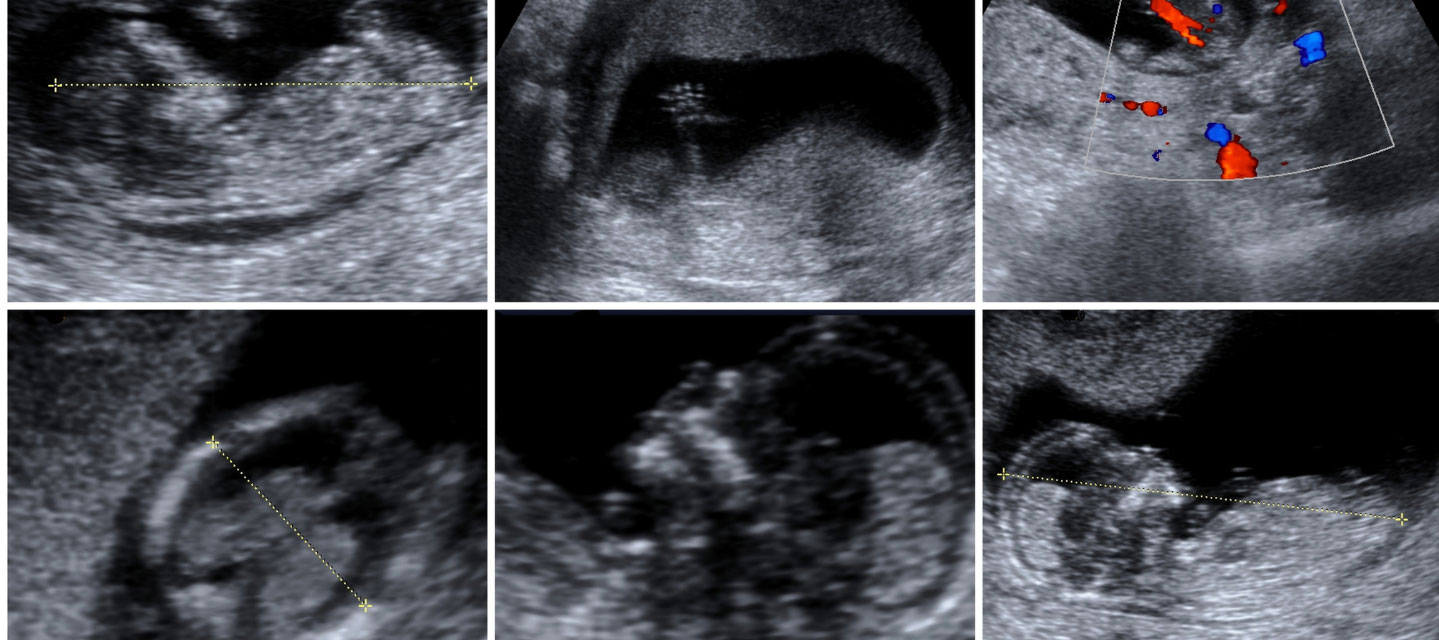

six sonographic images of a of an infant; diagnostic medical sonography

Diagnostic Medical Sonographers use high-frequency sound waves (ultrasound) to produce dynamic visual images of organs, tissues and blood flow inside the body.

Sonographers work closely with physicians by providing diagnostic images and a summary of technical findings to aid in reaching a medical diagnosis. This is a non-radiation modality, and it may be used on any patient, from unborn babies to the elderly. Sonographers may work in a hospital, a clinic, a physician’s office, education, sales or as an applications specialist.